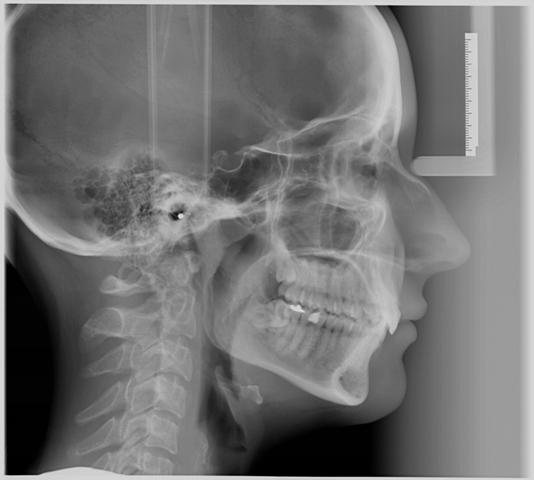

Zdjęcie cefalometryczne

służy do obrazowania części twarzowej czaszki, która uwidacznia struktury kostne, a także tkanki miękkie (zarys nosa, warg itp.) oraz zatoki przynosowe, co pozwala na wybór optymalnego aparatu ortodontycznego.